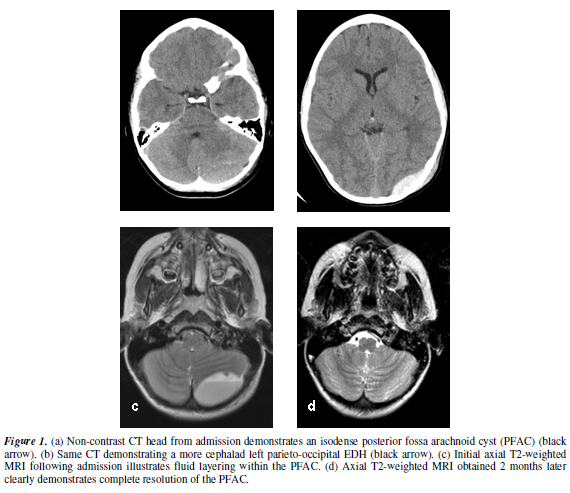

This eight year-old, previously healthy Caucasian female fell down approximately 10 steps, striking her head upon a concrete floor without loss of consciousness. She complained of headache and nausea and had one episode of non-projectile vomiting. She had no neurologic deficits. Cranial CT scan demonstrated a small, biconvex, left parieto-occipital epidural hematoma (EDH, Figure 1a) without evidence of overlying fracture or significant underlying mass effect. In addition, an iso-dense extra-axial fluid collection with a focal high-density region was noted in the left posterior fossa (Figure 1b). On magnetic resonance imaging (MRI), the cyst located in the posterior aspect of the left posterior fossa measured 38 x 25 x 17 mm in size and had moderate mass effect, effacing but not occluding the adjacent fourth ventricle (Figure 1c). No radiographic evidence of hydrocephalus was appreciated. The patient was observed in the pediatric intensive care unit for 72 hours without neurologic decline and with gradual resolution of her symptoms. She was managed non-operatively because of the absence of neurologic deficit or symptoms and the minimal mass effect associated with both the supratentorial and infratentorial lesions.

While they considered this

option, nausea and dizziness prompted another cranial CT scan three weeks later

that demonstrated complete resolution of the left parieto-occipital epidural

hematoma and the posterior fossa arachnoid cyst. Resolution of the cyst and

hematoma was verified by MRI at the two month follow-up visit (Figure 1d). The child was released to